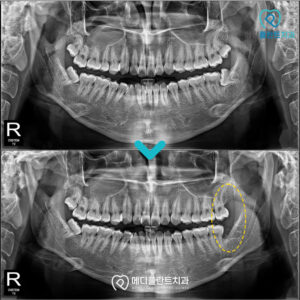

춘천수면사랑니, 두려움 때문에 발치를 미루고 있다면   . 안녕하세요:) 춘천수면사랑니치과 메디플란트치과입니다. . 치과 치료에 대한 두려움 때문에 발치를 미루는 분들이 생각보다 많습니다. . 사랑니는 구강 내부에서 세 번째 큰 어금니로 ‘제3대구치‘라고도 부르는데요. . 사람마다 1개부터 4개까지 맹출하는 개수가 다르며 아예 더보기…